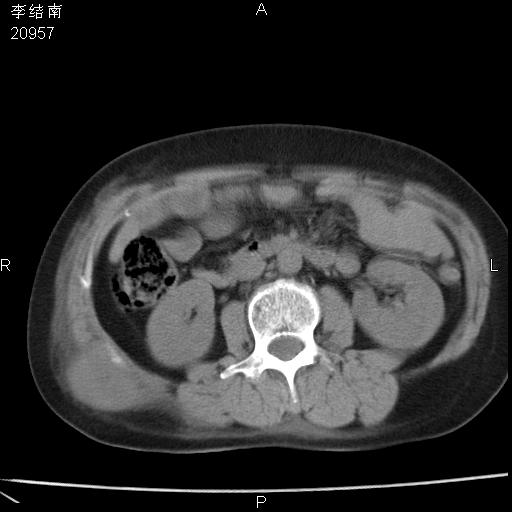

患者女,45岁,以右侧腰部包块来就诊,局部有压痛,皮肤颜色正常。因为是熟人扫的范围较大,患者有胆结石,胆源性胰腺炎病史。请大家看看,有手术病理。

可能大家觉得片子的质量不好,当时是做下腹部扫描,所以没有常规喝水,右腹壁的病灶当时是,密度不均有钙化影,局部骨质没见破坏,肝脏应该是受压的表现,所以当时考虑为腹壁的良性占位,各位老师考虑的神经源性肿瘤,我当时还真没想到,胰腺是胰腺炎治疗后改变.膈脚旁的混杂密度包快不好考虑什么,到上级医院做增强(腹部)+肺部平扫后,发现腹壁的病灶呈不均匀性强化局部可见囊性灶,当时考虑为腹壁结核,最具戏剧性的是膈脚旁的混杂密度灶确是胃的一部分,而腹壁的病灶确是脂肪瘤(简直不可思议)但是我亲眼所见在我们县医院开的.

很不好意思 ,患者后来手术切口裂开,临床医生作了病理证实是腹壁结核。

[病理诊断] CT13183腹壁结核!